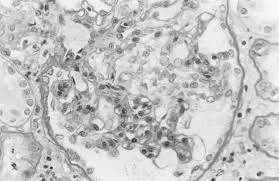

Injúria Renal Aguda (revisão Lancet 2025)

Injúria Renal Aguda (revisão Lancet 2025)